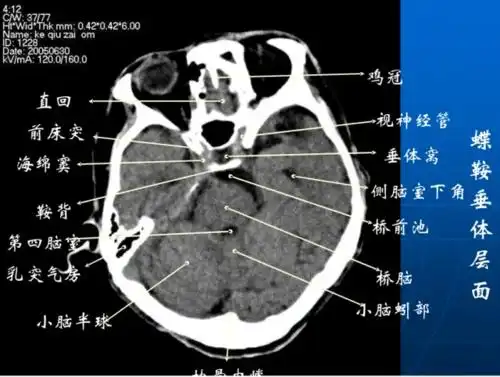

一套非常牛的「头颅ct解剖图谱」

头颅ct 解剖图谱,人手一份

头颅ct解剖与常见出血梗死判读

影像总结头颅ct基本知识与常见病变